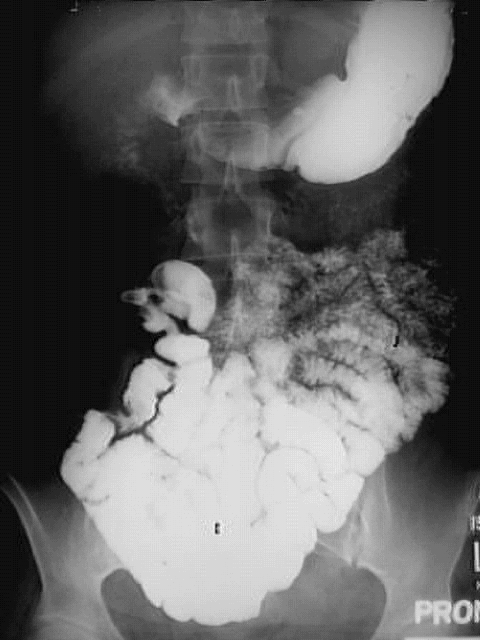

Abdomen- Small Bowel Follow Through: